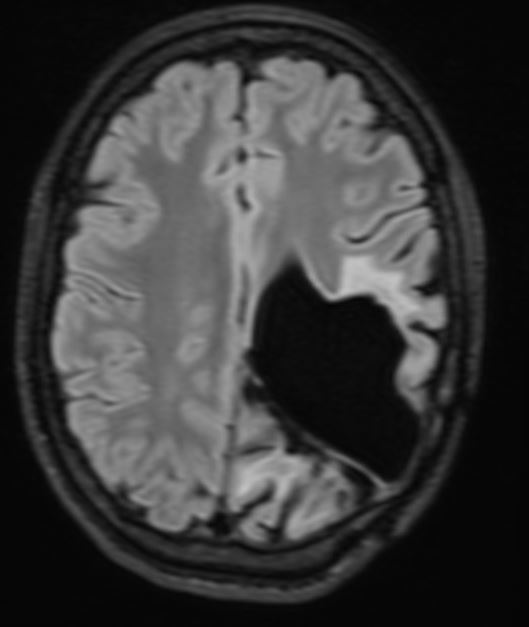

The patient presented with headache and vomiting and subsequently had surgery on three occasions for an intraventricular meningioma, with the following sequelae on MRI scan